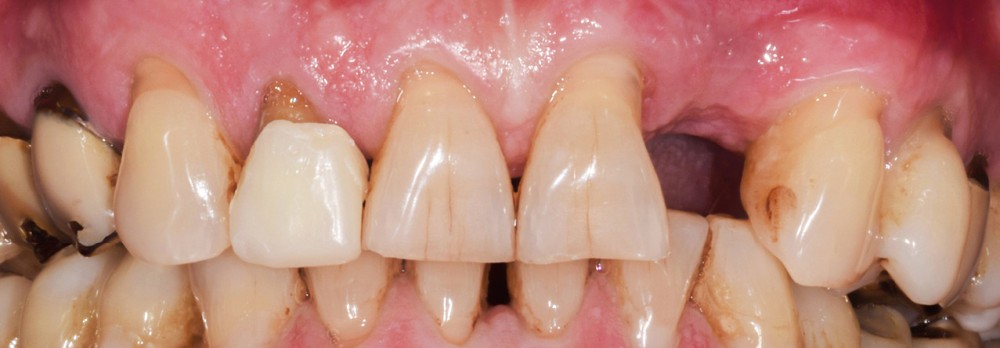

Situation initiale

Un patient de 62 ans se présente en consultation afin de réaliser les coiffes prothétiques des dents 12 et 22. La 12 présente une restauration par prothèse transitoire non adaptée. Un implant au niveau de la 22 a été posé par un autre praticien selon une technique chirurgicale en deux temps. Le praticien a adressé le patient pour la réalisation prothétique. L’option de bridge collé cantilever mono ailette n’avait pas été retenue ou proposée selon une technique chirurgicale en deux temps. Le patient souhaite rétablir l’esthétique et la fonction de ces deux dents uniquement.

Au vu des conditions initiales, il nous apparaît impossible de restaurer une esthétique satisfaisante, notamment au niveau de l’alignement des collets, sans une chirurgie muco-gingivale associée à une réhabilitation des dents antérieures par facettes. En effet, la perte de la 22, associée à une forme triangulaire des dents, a provoqué un non-alignement des collets ainsi que la présence de trous noirs entre les dents 21-22 et 22-23. Cependant, les contraintes exprimées par le patient contre-indiquaient ce traitement.

La proposition thérapeutique retenue par le patient est donc une réhabilitation par couronne céramique sur 12 (dento-portée) et 22 (implanto-portée). Ce choix thérapeutique impose de concevoir des dents qui s’intègrent au mieux dans l’harmonie du sourire, tout en étant conscient des limites d’un tel traitement.